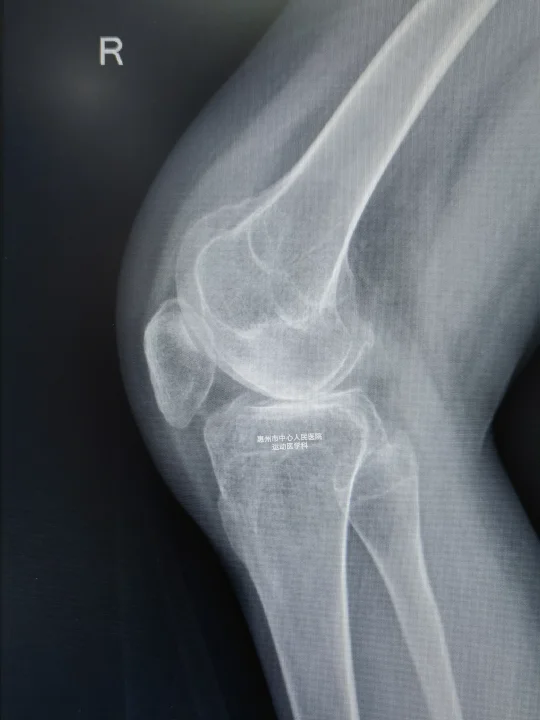

X线拍完,诶,这是典型的类风湿关节炎的表现,关节间隙明显变窄,关节软骨面明显破坏硬化,但是没有骨赘,软骨下骨破坏还不要严重。